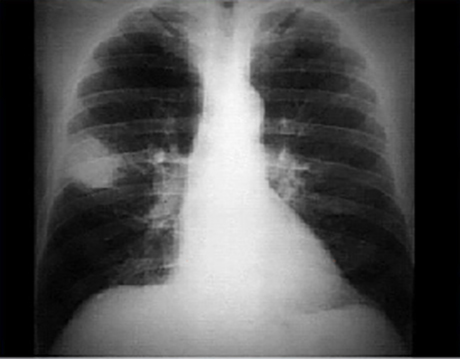

PA

In this PA view, there is a peripheral 6 x 4.5 cm radiodensity or infiltrate in the right upper lobe. The infiltrate is free of any contained calcification or stranding into the adjacent pulmonary parenchyma. Atelectasis and signs of hilar adenopathy are also absent. The cardiac silhouette, pulmonary vasculature and bony structures are normal.